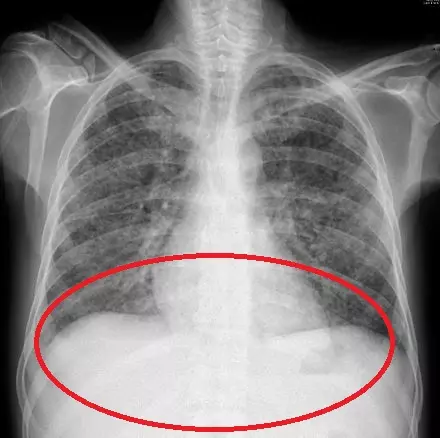

검사 결과, 대변과 폐에서 채취한 검사물에서 분선충이 발견됐다. 회충의 일종으로, 피부를 통해 체내에 침투해 발진과 복통 등을 유발한다. 주로 맨발로 흙을 밟았을 때 흙 속에 있던 유충이 피부를 뚫고 몸 안으로 들어간다. 특히 면역력이 떨어진 사람에게 치명적일 수 있다.

의료진은 “남성은 알코올 중독과 당뇨병 등을 앓으며 면역력이 떨어진 상태에서 기생충에 과감염됐다”며 “이는 전신으로 기생충이 퍼져 생명을 위협하는 상황”이라고 말했다. 남성은 과감염 확진 이후 기생충 약인 이버멕틴 치료를 받았지만, 치료 중 폐출혈과 패혈증으로 결국 사망했다.